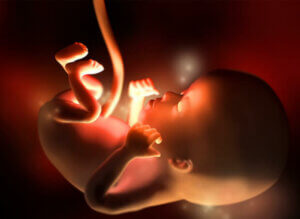

12. raskausviikko

12. raskausviikko on ensimmäisen raskauskolmanneksen viimeinen viikko. Noin 4-5 sentin pituisen ja 5-10 gramman painoisen sikiön sydän sykkii jo voimakkaasti, noin 160 lyöntiä minuutissa. Nyt noin luumun tai passionhedelmän kokoinen sikiö kasvaa 11. ja 12. raskausviikon aikana 15 %.

Tässä vaiheessa raskautta sikiön liikkeet alkavat lisääntyä, vaikka odottava äiti ei niitä vielä tunnekaan. Sikiön raajat ovat jo muodostuneet ja sisäelimet alkavat kehittyä nopeasti. Suolisto, joka on tähän asti ollut yhteydessä napanuoraan, on nyt siirtynyt vatsaonteloon. Sikiön pää alkaa muotoutua pyöreämmäksi ja korvat siirtyä lopullisille paikoilleen. Sikiö pystyy jo avaamaan ja sulkemaan suunsa, haukottelemaan, nielemään ja nikottelemaan. Sen kynnet ja äänihuulet alkavat muodostua. 12. raskausviikon aikana sikiön munuaiset alkavat tuottaa pieniä määriä virtsaa, ja myös ensimmäisiä ihokarvoja alkaa ilmaantua.